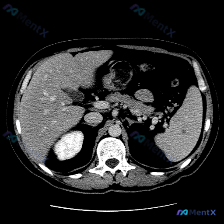

这是一张腹部横断面增强CT(软组织窗),图像质量良好:

- 脾脏:大小、形态完全正常,密度均匀,未见明确占位性病变;

- 肝脏:是唯一有阳性发现的器官——肝实质内可见数个低密度灶,边界尚清;

- 其他:胰腺、双侧肾上腺区、腹膜后间隙、所见胸腰椎均未见明显异常;腹主动脉管壁光滑,管径正常。